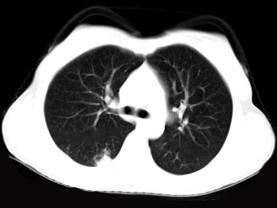

问题 女,40岁,间断咯血一周,低热,行胸部CT扫描如图,选择最可能的诊断为 ( )

选项 A、支气管囊肿并感染 B、肺脓肿 C、肺部感染 D、支气管扩张并感染 E、肺结核

答案 E